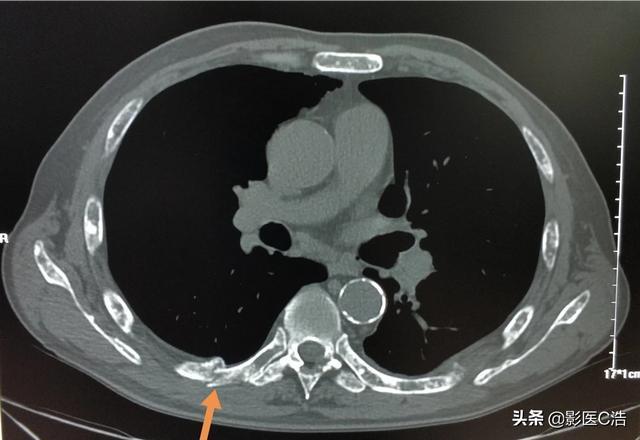

Des fractures pathologiques peuvent également se produire lorsque des métastases se développent dans l'os, généralement dans les côtes, parce que les métastases détruisent la structure normale de l'os, le rendant faible et susceptible de se fracturer lorsqu'une force externe est appliquée. Certaines métastases osseuses peuvent également se présenter sous la forme de masses de tissus mous autour de l'os, mais elles ne sont pas faciles à détecter car elles ne sont pas à la surface du corps. Fracture pathologique (flèches ci-dessous)

Quel est le meilleur moyen de savoir si vous souffrez d'une douleur métastatique ou non métastatique ? Rappelez-vous que la douleur métastatique osseuse est généralement incessante et progressive et qu'elle évolue plus rapidement. Certaines personnes disent qu'elles ont des douleurs à l'épaule depuis des années, alors ne vous inquiétez pas pour les métastases car les tumeurs ne sont pas aussi gentilles et patientes.